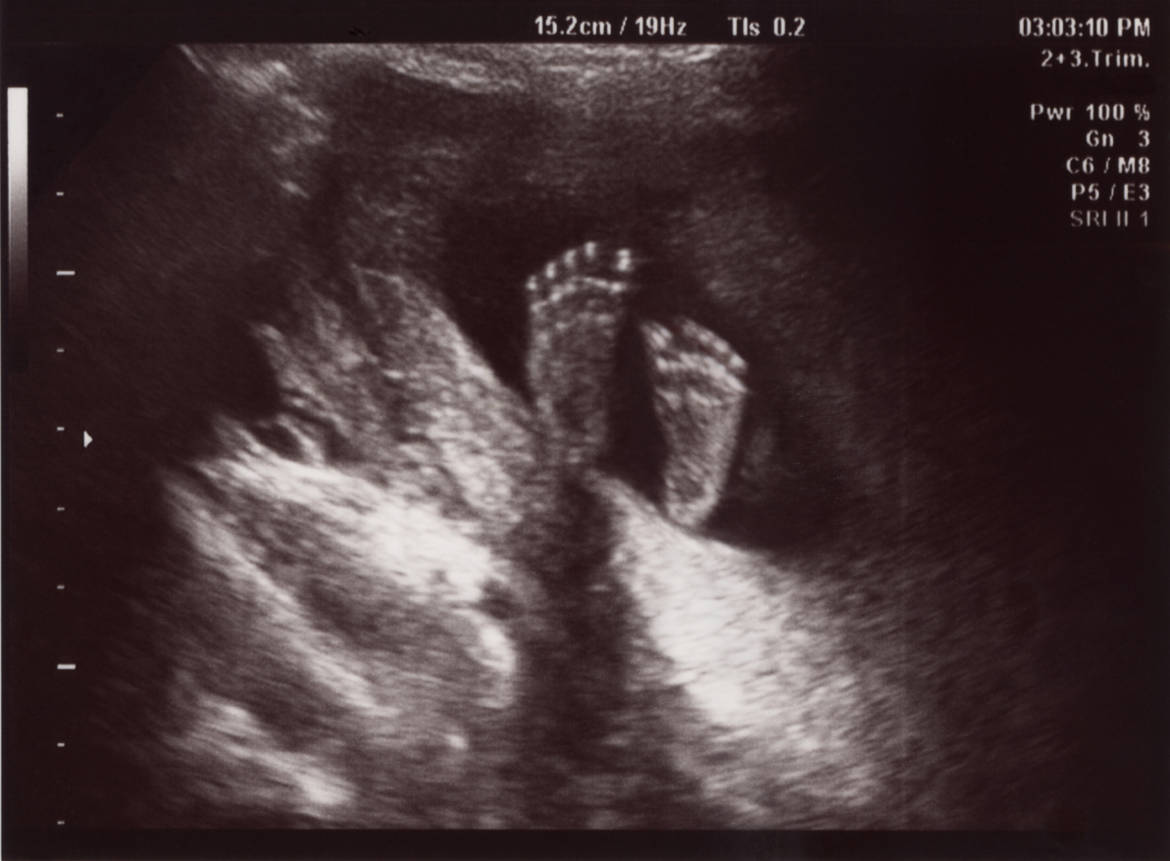

Dans de rares cas, lʹinfection de la mère au Covid-19 peut être à lʹorigine de lésions cérébrales ou même de la mort du fœtus.

Cʹest le résultat d'une étude menée par une équipe de chercheuses et chercheurs du Centre hospitalier universitaire vaudois (CHUV), de l'Université de Lausanne (Unil), du Réseau hospitalier neuchâtelois et de la Haute école de santé Vaud.